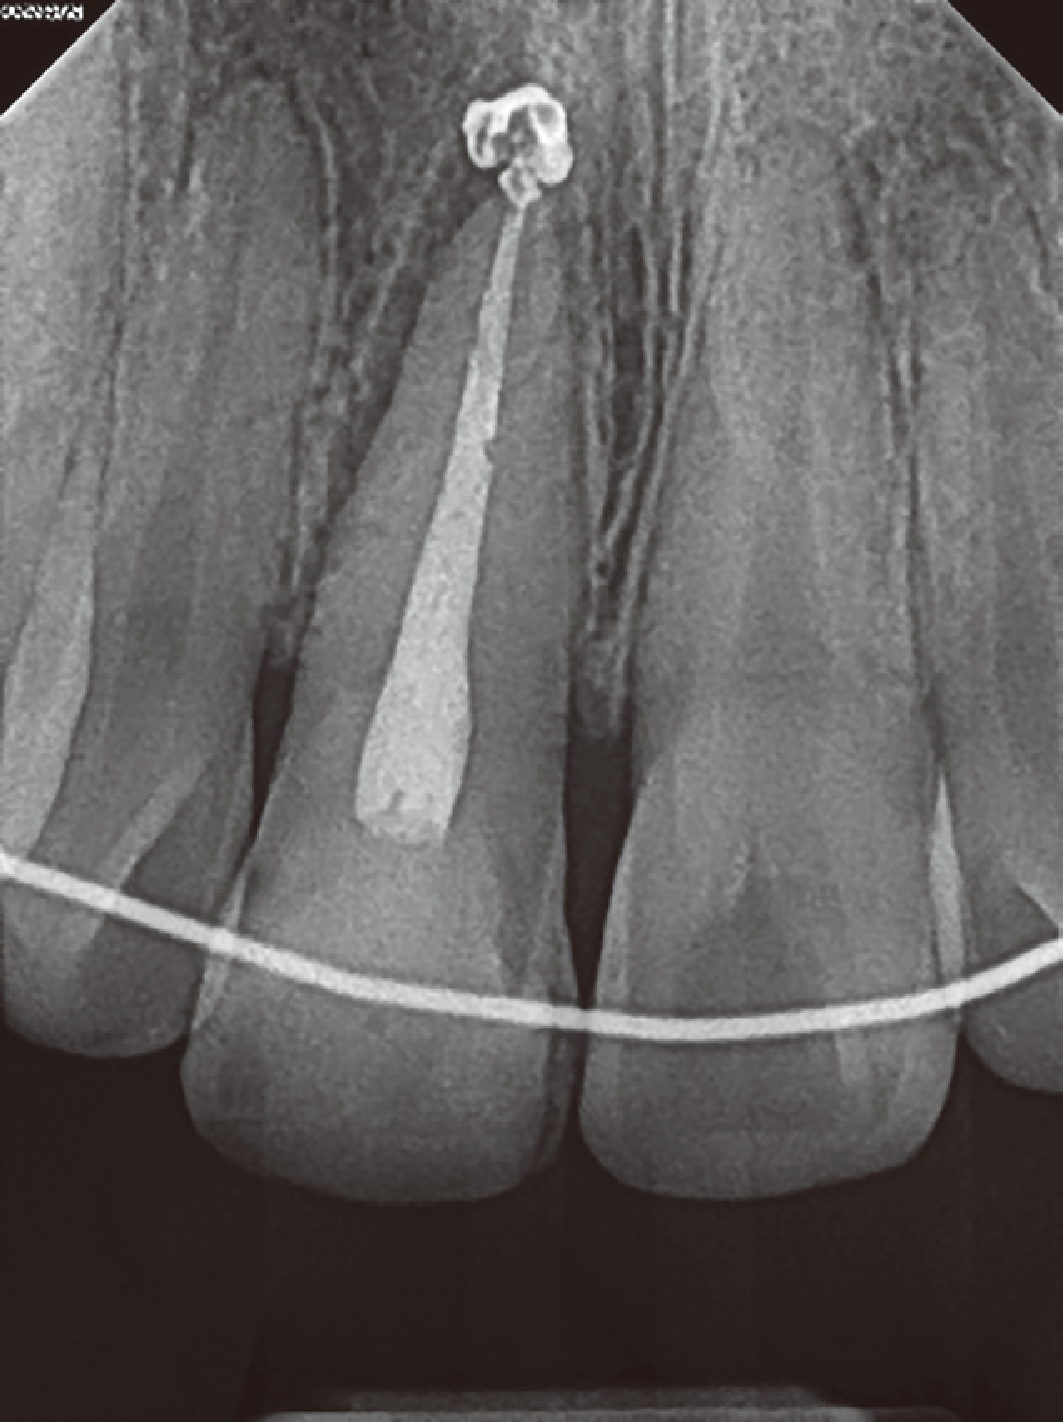

Fig. 1

(A) Preoperative radiograph of maxillary right central incisor. (B) Photograph of palatal probing depth on maxillary right central incisor.

28세 남자 환자가 3일 전 넘어져서 치아가 부러졌다는 주소로 내원하였다. 외상 발생 다음날 개인 치과에서 파절편 제거, 발수 및 근관 성형 시행 후 본과로 의뢰되었으며 임상 검사 및 방사선 검사 상 우측 상악 중절치의 치수강을 침범한 치관-치근 파절이 관찰되었다. 파절선은 협면 절단측 1/3 경계에서 시작하여 구개측 치은연하로 연장되었으며 5 - 6 mm의 치주낭 깊이를 보였다. 동요도는 없었으나 잔존 치관부에 균열선이 관찰되었으며 타진 및 촉진에 통증을 호소하였다(Fig. 1). 이에 따라 우측 상악 중절치의 복잡 치관-치근 파절로 진단하였다. 첫 내원일에 추가적인 근관 성형과 세정을 시행하였다. 해당 치아에 러버댐 격리를 위한 클램프를 직접 적용하면 통증을 유발할 수 있기 때문에 상악 양측 견치에 클램프를 적용하여 격리를 시행하였다. 근관치료를 위한 국소마취를 시행하지 않았음에도 근관 내 기구조작에 통증을 호소하지 않았다. 페이퍼 포인트를 적용하였을 때 근관 건조가 잘 되는 것을 확인하고 수산화칼슘 첩약 후 임시가봉을 시행하였다. 환자가 심미적 불편감을 호소하여 협측 치관 파절 부위에 레진 수복을 추가적으로 시행하였다. 치아에 대한 전반적인 평가를 시행한 후 환자에게 구개측 치은 연하로 연장된 파절선에 대한 처치가 필요하며 이를 위해 교정적 정출술과 외과적 정출술 중에 선택할 수 있음과 각각의 방법, 기간 및 장단점에 대해 설명하였다. 환자는 치료를 단기간에 끝내야 하고, 재발의 위험성이 적은 방법을 선호하여 외과적 정출술을 시행하기로 결정하였다. 또한, 치아의 구개측 파절선이 협측에 비해 치은연하로 연장된 형태이기 때문에 외과적 정출술을 시행할 때 180°회전 식립하여 협설측 치조골의 높이 차이를 이용해 정출량을 감소시키고 치근 길이를 더 확보할 수 있음을 설명하였다.